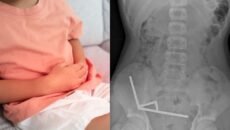

কিশোরের পেটে মিলল ১০০ শক্তিশালী চুম্বক